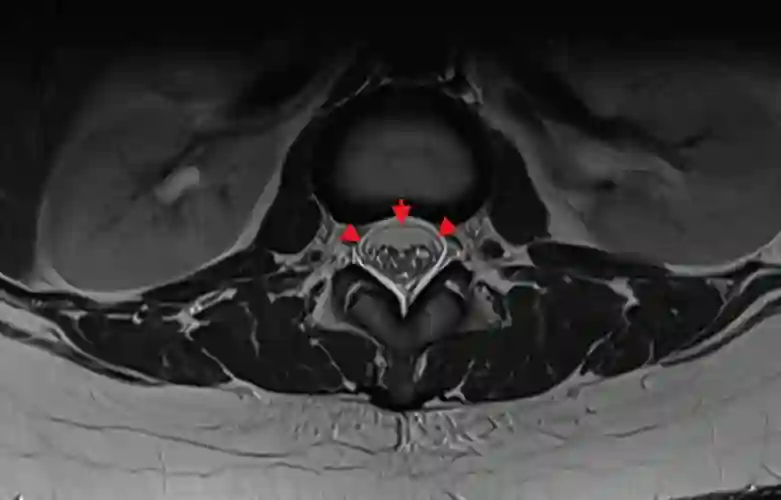

Duradoppelkontur axiales MRi

Darstellung einer duralen Doppelkontur (SLEC), markiert mit roten Pfeilen in einem axialen T2 MRI Bild der thorakalen Wirbelsäule.